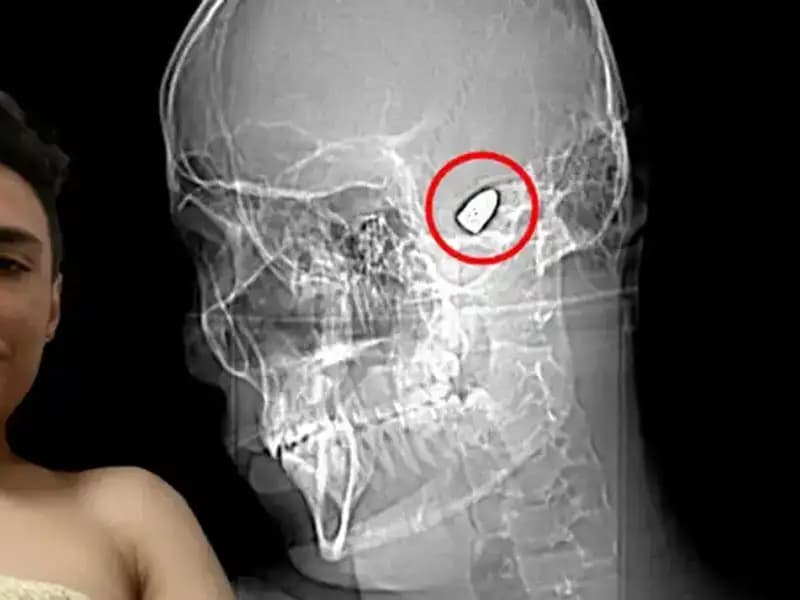

Kafasında Patlayıcı Var: Psikolojik Sorunları ile Savaşan Bir Genç